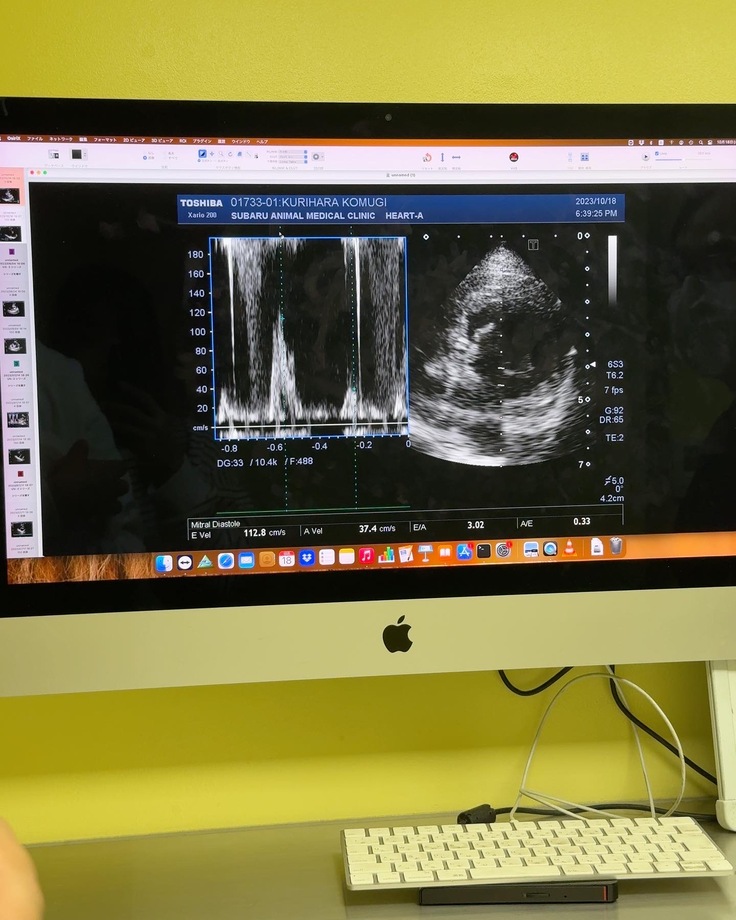

今日は定期検診に行ってきました🐶

検診の結果はかなり心臓が肥大してきており、投薬治療ではかなり限界の域まで来ているとのことでした。

少しでも早く手術を受けさせてあげてくださいと言われました。

もうこむぎには残された時間は少ないかもしれません。

明日容体が急変してもおかしくない。